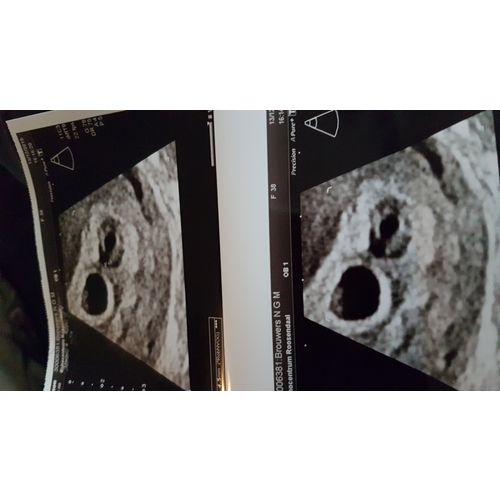

Hier ook een echo gehad met 6.5 weekjes

Oei wat leuk een meerling voor jullie 👶👶